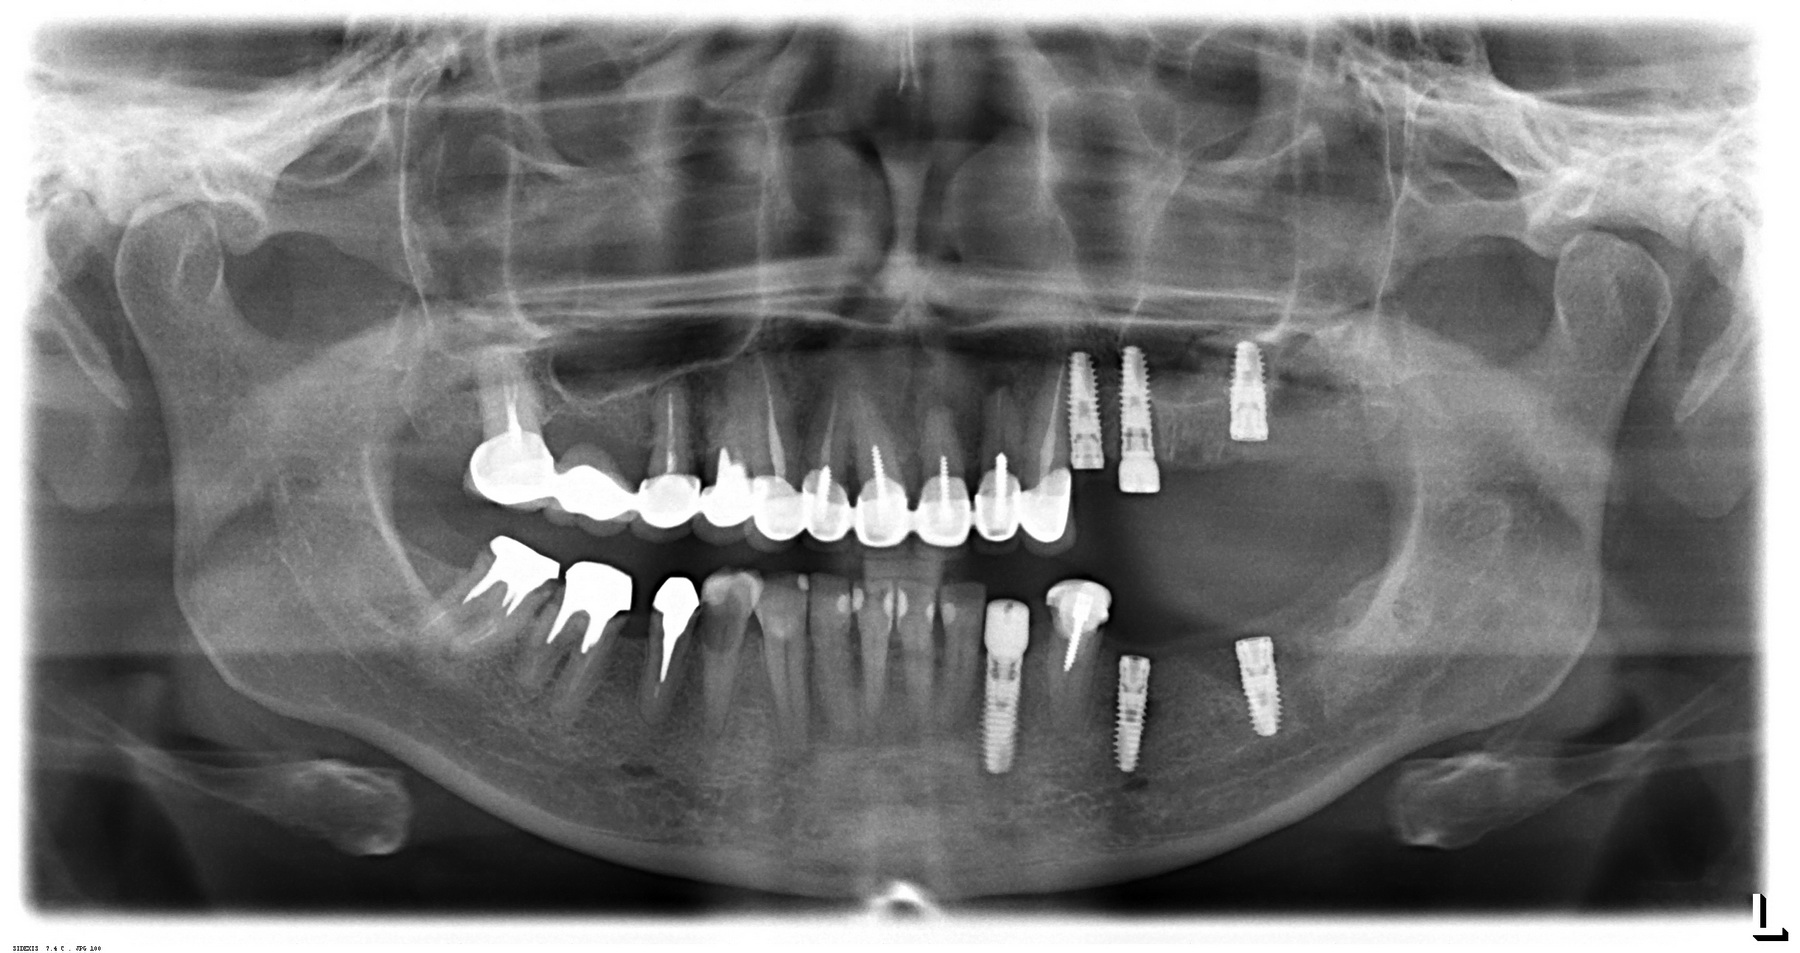

Вот пример. На этот раз, на снимках: пациентка, возрастом чуть больше сорока лет. После диагностики и необходимых исследований стало ясно, что необходимо хирургическое лечение во всех участках зубного ряда. В частности, удаление 13 зубов, включая ретинированный зуб мудрости, остеопластика на нижней челюсти и синуслифтинг, пластика слизистой и много чего еще.

Представьте, сколько времени займет хирургическая операция, если делать хотя бы половину этой работы за один раз? Как себя будет чувствовать пациентка во время и после хирургической операции? Как будет себя чувствовать доктор, какова вероятность критической усталости к концу операции? Как поддерживать анестезию и чистоту полости рта в течение такого длительного времени? И сколько будет стоить такая операция?

У меня нет ипотеки и других долгов, поэтому я принимаю решение разбить весь объем хирургического лечения на четыре этапа — по одному в каждом из сегментов зубного ряда. И начинаю я… угадайте, с какого участка? Верно, с того, который уже не функционален из-за критического разрушения зубов — с левого нижнего:

Операция заняла всего 60 минут, послеоперационные явления были настолько незначительны, что пациентка чуть ли не через пару недель решилась на вторую операцию:

в ходе второго этапа было установлено три импланта в боковом сегменте верхней челюсти, удален ретинированный зуб мудрости, проведен синуслифтинг

Вторая операция заняла чуть больше времени (90 минут), поскольку потребовалось удаление ретинированного зуба мудрости и синуслифтинг. Послеоперационные явления более выраженные — отек держался в течение нескольких дней, болезненных ощущений почти не было.

Стоит ли сейчас приступать к третьему и четвертому этапам, а именно — к удалению зубов и имплантации на правой стороне? На мой взгляд, нет. И тут срабатывает принцип, поспешишь — людей насмешишь. Ну подумайте сами — у пациентки не интегрированы импланты с левой стороны, вся жевательная нагрузка приходится на правую сторону. Удалив зубы, мы сильно увеличим нагрузку на оставшиеся передние сегменты, которые, если честно, находятся не в лучшем состоянии. И это не говоря о том, как пациентка будет себя чувствовать, не имея возможности нормально пережевывать пищу. Поэтому в наших интересах — дождаться интеграции имплантов слева, установить на них временные протезы, перенести на них жевательную нагрузку, и только потом приступать к работе на правой стороне.

И тут пациентка сказала: «Постойте! У меня так легко проходят операции, так почему бы нам не поставить большее количество имплантов в правой части? В идеале, чтобы каждая коронка опиралась на свой имплантат — я больше не хочу мостовидные протезы!» Желание пациента — закон. Поэтому на правой стороне мы усложняем работу:

третий этап работы: слева уже установлены временные протезы на имплантах, а справа удалены четыре зуба и одновременно установлены четыре импланта

Как вы думаете, сколько времени заняла третья хирургическая операция? 60 минут! Легко, быстро и комфортно. А главное — результативно!

Что в итоге получилось? Пока три этапа, по 60-90 минут каждый. Минимум времени операции, минимум травмы. Как результат — успешное комфортное лечение с высокой эффективностью и без больших единовременных затрат. Это всяко лучше, чем одна многочасовая дорогостоящая операция с тяжелым послеоперационным периодом и существенным дискомфортом. Вот вы бы что выбрали?